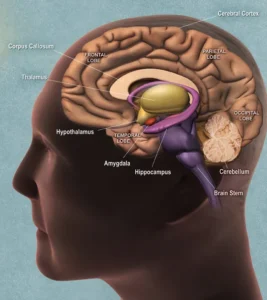

BRAIN:

The brain is the body’s control center. It forms the core of the central nervous system by creating, sending, and processing nerve impulses, thoughts, emotions, physical sensations, and more.

The skull encloses the brain, protecting it from injury.

Neurologists are doctors who study the nervous system. Over time, they have identified numerous parts of the brain, including systems within the brain that function similarly to independent organs.

The brain is made up of three main subparts: the cerebrum, the cerebellum, and the brainstem. Within these areas, there are several key components of the brain that, together with the spinal cord, comprise the central nervous system.The major areas of the central nervous system include:The medulla: This is the lowest part of the brainstem. It helps control heart and lung function.

The pons: Located above the medulla in the brainstem, this area helps control eye and facial movement.

The spinal cord: Extended from the base of the brain and down the center of the back, the spinal cord helps with many automatic functions, such as reflexes. It also sends messages to and from the brain.

The parietal lobe: Situated in the middle of the brain, the parietal lobe supports the identification of objects and spatial reasoning. It also plays a role in interpreting pain and touch signals.

The frontal lobe: The frontal lobe, which is located in the front of the head, is the largest section of the brain. It plays a role in many conscious functions, including personality and movement. It also helps the brain interpret smells.

The occipital lobes: Positioned near the back of the brain, the occipital lobe primarily interprets vision signals.

The temporal lobes: Located on either side of the brain, the temporal lobes play a role in numerous functions, including speech, scent recognition, and short-term memory.

The brain’s two halves are called the right and left hemispheres. The corpus callosum connects these two hemispheres.